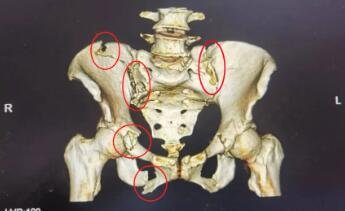

骨盆环存在多处骨折

刚经历过肋骨骨折复位手术的王阿姨骨盆环存在多处骨折,复杂的骨盆骨折复位手术需要对骨盆深层结构进行广泛剥离暴露,术中可能会伤及盆腔大血管和神经,且因手术损伤大、出血量多,感染的风险增加,再加上需长期卧床易导致多种并发症。种种不利因素叠加起来,令手术难上加难,风险可想而知。